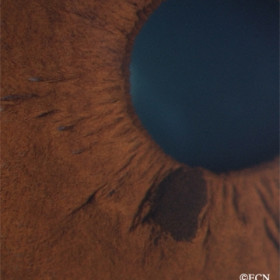

Iris Melanoma

Iris Melanoma - Gonioscopy reveals the pigmented iris tumor arising from the iris stroma. It is seen to extend from the ciliary body band into the pupil.